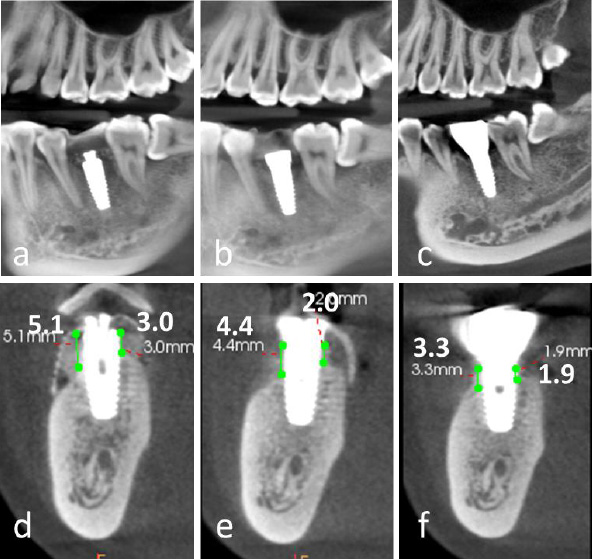

2.11. Alveolar Ridge Augmentation

A significant increase in both the width and height of the alveolar ridge was achieved. A transmucosal healing abutment was placed for two weeks, followed by the completion of a single-tooth implant restoration, resulting in satisfactory aesthetic and functional outcomes (Fig. 4d-4i). Postoperatively, the vertical bone height on the buccal side increased by 5.1 mm and on the lingual side by 3.0 mm (Fig. 5a-5f). Slight reductions in these measurements were observed upon completion of the implant restoration, with the buccal and lingual vertical bone heights measuring 4.4 mm and 2.0 mm, respectively (Fig. 5b, 5e).

At the 2.5-year follow-up, the vertical bone height on the buccal side was maintained at 3.3 mm, while the lingual side measured 1.9 mm (Fig. 5c, 5f).

Comparative analysis of cone-beam computed tomography (CBCT) imaging at different treatment stages. (a-c) Panoramic reconstructed views: (a) Immediate postoperative evaluation, (b) Healing abutment placement phase, (c) 2.5-year follow-up after prosthetic delivery, (d-f) Cross-sectional views corresponding to respective treatment phases, (d) Postoperative implant positioning, (e) Peri-implant tissue maturation during healing phase, (f) Long-term (2.5-year) evaluation of peri-implant bone stability and prosthetic integration.